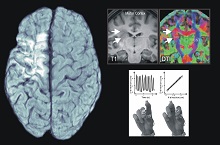

Functional imaging (PET, MRI) and electrophysiological methods (EEG, TMS, tDCS) are combined with computational approaches to achieve a better understanding of i) the development of normal brain functions during ageing, ii) disease-induced dysfunction, and iii) cerebral plasticity and recovery of function.

Results help to decode how the human brain enables higher cognition and to develop novel therapeutic approaches.